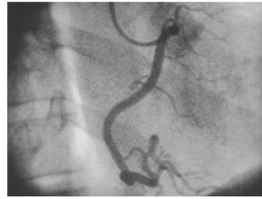

Right coronary artery

The posterior interventricular (descending) artery (portion of the right coronary artery)

Paralelled by middle cardiac vein

Left coronary artery

From behind Left Cusp of Aortic Valve

Circumflex branch

The circumflex branch typically gives of three **obtuse marginal** branches

**Anterior interventricular artery (LAD)** ## Footnote Really important, supplies 2/3 of the interventricular septum

**Great cardiac vein** parallels the LAD ## Footnote Leads into the coronary sinus - coronary sinus leads to right atrium